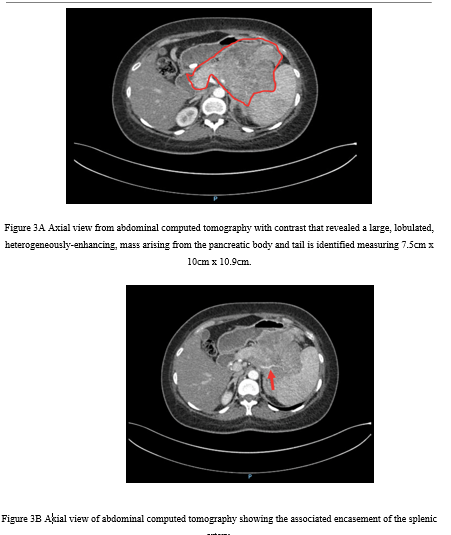

Computed tomography (CT) of the chest revealed multiple non-calcified subcentimeter pulmonary nodules (Figure 2). CT of the abdomen demonstrated a 7.5 × 10 × 10.9 cm lobulated, heterogeneously enhancing mass in the pancreatic body and tail (Figure 3A), invading the gastric fundus and encasing the splenic artery (Figure 3B), worrisome for malignancy.

Figure 3A Axial view from abdominal computed tomography with contrast that revealed a large, lobulated, heterogeneously-enhancing, mass arising from the pancreatic body and tail is identified measuring 7.5cm x 10cm x 10.9cm.

Figure 3B Axial view of abdominal computed tomography showing the associated encasement of the splenic artery.

The patient received aggressive potassium replacement and was initiated on insulin therapy. Surgery would have been the best option if the tumor was removable, but the situation was far more complicated. The mass was unusually large, pressing on the stomach (lesser curvature, body, and fundus) and the hilum of the spleen. It also encased the splenic artery, which made complete resection nearly impossible and raised serious concerns about the risk of major surgical complications.